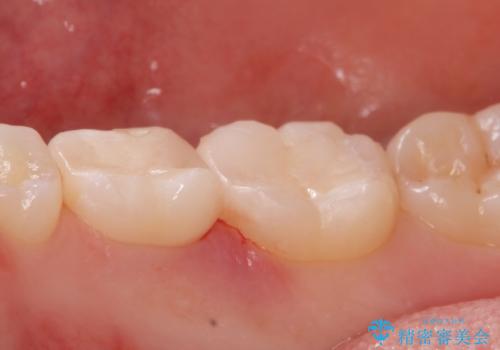

レントゲンを撮影したところ虫歯がありましたので拡大鏡下で虫歯を取り除いた後、e-maxインレーにて治療を行いました。

手前の歯は乳歯でしたが、患者様と相談しなるべく長持ちさせたいとの事でしたのでe-maxインレーでの治療となりました。

適合の良い詰め物が入りました。